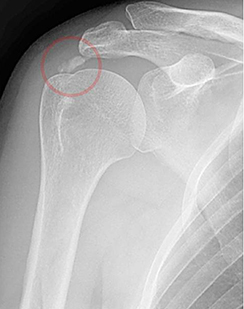

석회성 건염

• 힘줄에 석회가 침착되어 심한 통증을 유발합니다.